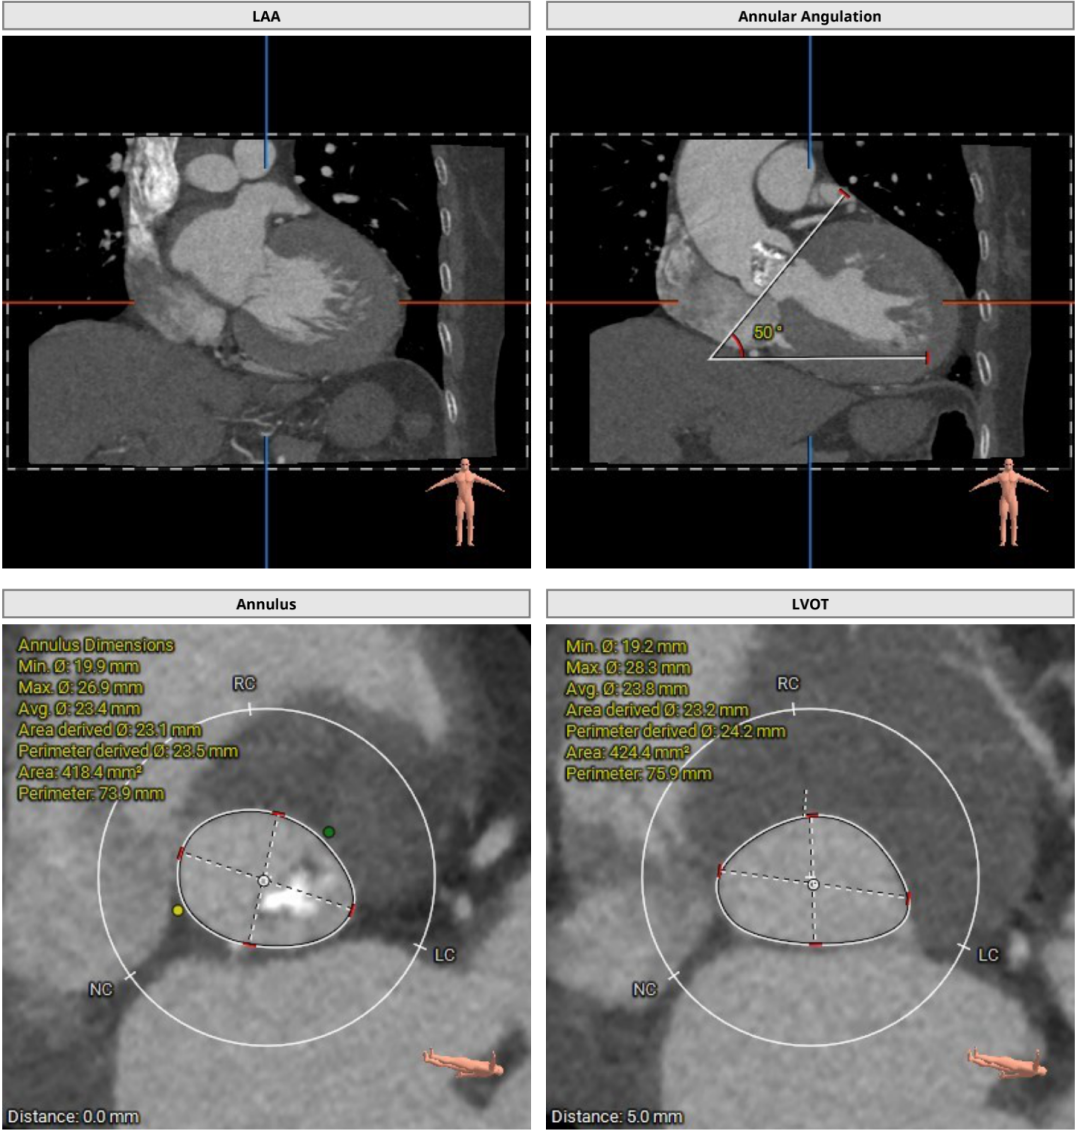

术前CT评估

1.Type0型二叶式主动脉瓣,左右冠同窦,瓣叶增厚伴中重度钙化,钙化主要分布于无窦与左窦交合缘及瓣叶边缘;LVOT呈类直筒状形态;

2.冠脉开口高度尚可,左冠瓣叶稍冗长,切线位左冠瓣叶长度稍大于冠脉开口到瓣叶根部附着缘距离 ;

3.瓦氏窦、窦管交界内径正常,升主动脉扩张;左室腔内径可,心室壁增厚;

4.主动脉瓣环与水平面夹角为62°,横位心,主动脉弓部夹角,弓距尚可;

主动脉根部测量

随着TAVR技术在国内的普及,主动脉瓣狭窄患者有了更多的治疗选择。本例患者为主动脉瓣重度狭窄伴轻度反流,患者伴代偿性心力衰竭,术前评估适宜行TAVR手术,有TAVR手术指征。术前CT分析提示患者为Type0型二叶式主动脉瓣,瓣环径23.5mm,瓣叶增厚伴重度钙化,钙化主要分布于无窦与左窦交合缘及瓣叶边缘,LVOT呈类直筒状形态,预估人工瓣膜会有较明显形变,有根部撕裂、损伤风险。左室流出道可提供辅助锚定,综合预估瓣膜锚定定位精度要求较高。患者又为横位心,主动脉弓距及夹角尚可,升主动脉扩张,需警惕血管夹层、破裂等风险,对经导管主动脉瓣输送系统过弓、跨瓣的性能要求较高。综合以上因素,该患者行TAVR手术对术者快速、精准的操作能力及手术团队的密切配合要求较高。广东省人民医院赣州医院(赣州市立医院)倪忠涵院长带领团队,经过心内科、心外科、麻醉科、超声等多学科团队的缜密讨论,最终决定为患者施行TAVR手术治疗。